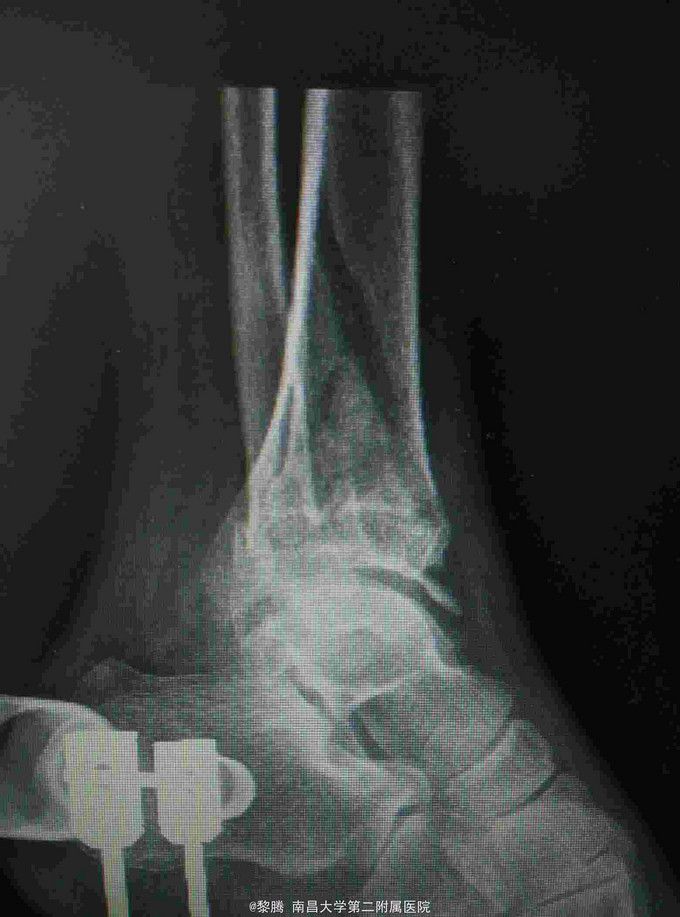

摔伤致左足肿痛,活动受限半天 患者中年男性,因不慎摔倒左足着地,出现左足肿胀疼痛,伴有明显活动受限,无开放性伤口患者伤后未诉明显左足感觉异常。伤后急诊入我院就诊。

查体:左足及左踝关节肿胀明显,局部压痛明显,局部皮肤可见张力性水泡,左踝关节活动受限明显,足背动脉搏动存在,无明显感觉异常。 辅查:踝关节正侧位片提示胫腓骨远端骨折

诊断:Pilon骨折 治疗:骨折切开复位内固定